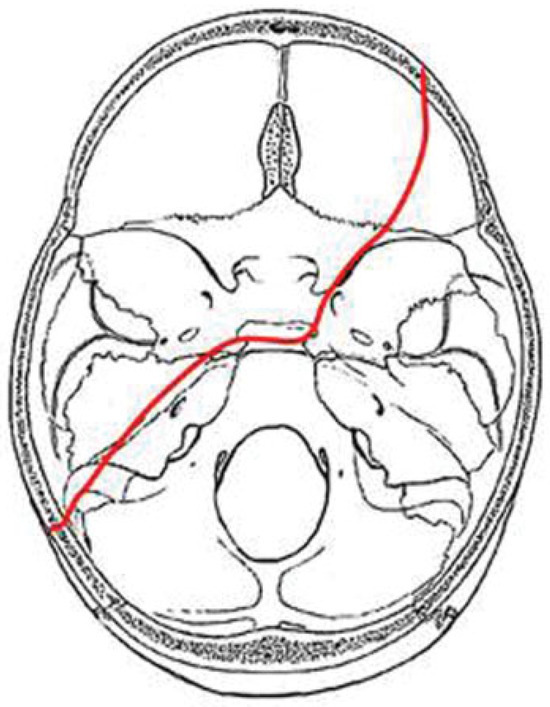

In our study we identified four major fracture patterns of transsphenoidal basilar skull fractures, which were: anterior transverse (AT), lateral frontal diagonal (LFD), posterior trans-verse (PT), and mastoid diagonal (MD), which matches Clark’s descriptions of the transsphenoidal basilar skull fractures.17

AT Pattern

The key to the identification of the AT pattern is the demon-stration of a coronal fracture through the sphenoidal plane at the base of the anterior clinoid processes. The exact position across the anterior sphenoid body varies slightly from the sphenoidal limbus to the roof of the extreme posterior ethmoid air cells. Most fractures pass through the roof of the sphenoid sinus anteriorly. The fracture typically begins in the squamous portion of the temporal bone, courses anteriorly to the sphenotemporal buttress, and then proceeds medially along the orbital surface (vertical plate) or the anterior cerebral surface (horizontal plate) of the sphenoid bone. The fracture intersects the sphenoid body at or slightly posterior to the junction, with the ethmoid bone producing the characteristic transverse fracture across the posterior aspect of the floor of the anterior cranial fossa. The fracture exits the sphenoid body through a similar pathway involving the contralateral greater wing along the orbital surface (horizontal plate) or the anterior cerebral surface (vertical plate). In severe fractures, the fracture will continue to propagate into the contralateral squamous portion of the temporal bone (Figure 5).

Figure 5. Composite drawing of the anterior transverse fracture pattern (left impact).